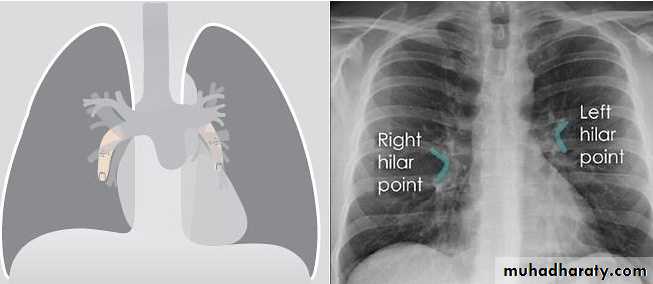

Hilar enlargement : The normal hilar opacities are composed of pulmonary arteries and veins.

The main lower lobe arteries are typically 9–16 mm in diameter.

Hilar lymph nodes cannot be identified as separate opacities on CXR and the walls of the central bronchi are too thin to contribute to any extent to the bulk of the hilar structures.

Vascular enlargement often: demonstrates a branching pattern, is typically bilateral and may be accompanied by cardiac enlargement.

Hilar masses are nearly always due to either lymph node enlargement or carcinoma of the bronchus. In practice, if there is any clinical doubt the patient will have CT for further evaluation.

Identify main lower lobe pulmonary arteries: They can be compared to a little finger pointing downwards and medially. Sometimes, usually on the left side – it can appear only as the proximal phalanx of the finger.Interpretation: If the little finger shadow of the right lower lobe artery is not seen then you must check for evidence suggesting collapse of the right lower lobe.Identify the hilar point: Look for the site where the most superior upper lobe vessel – either vein or artery – crosses the lateral margin of the little finger. The point of crossing is known as hilar point and forms a horizontal “vee” (> or <).Interpretation: The left hilum must never be lower than the right hilum. Whenever a left hilum appears lower than the right hilum – look for other evidence suggestive of: 1- Collapse of either the left lower lobe or of the right upper lobe or 2- Enlargement of the right hilumBilateral hilar LNE